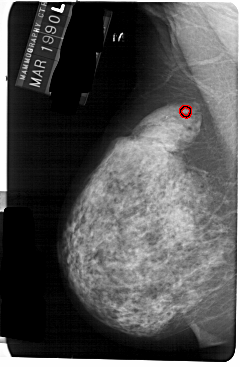

A_1148_1.LEFT_MLO

LEFT_MLO LINES 5491 PIXELS_PER_LINE 3586 BITS_PER_PIXEL 12 RESOLUTION 43.5 OVERLAY

FILE: A_1148_1.LEFT_MLO.OVERLAY

TOTAL_ABNORMALITIES 1

ABNORMALITY 1

LESION_TYPE CALCIFICATION TYPE PLEOMORPHIC DISTRIBUTION CLUSTERED

ASSESSMENT 4

SUBTLETY 2

PATHOLOGY MALIGNANT

TOTAL_OUTLINES 1

BOUNDARY